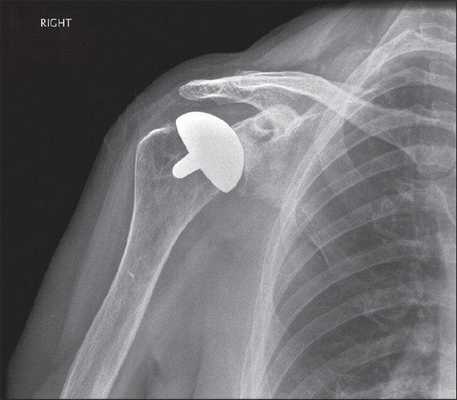

- Частичное протезирование суставной поверхности головки плеча является современной альтернативой реконструкции при значительном дефиците головки плеча

• Варианты хирургического лечения клинически значимых сцепляющихся дефектов 25-40% суставной поверхности головки плеча в литературе варьируют в широких пределах. Это открытые передние вмешательства, например, открытое перемещение капсулы, призванное ограничить объем наружной ротации и предотвратить тем самым сцепление дефекта головки с суставной впадиной. Это ротационная проксимальная остеотомия плеча, перемещение в дефект подлопаточной мышцы с тем, чтобы сделать его внесуставным, или артроскопический ремплиссаж. Также это заполнение дефекта таким образом, чтобы устранить условия для его сцепления. С этой целью выполняется пластика кортикально-губчатым трансплантатом из подвздошного гребня, костно-суставным аллотрансплантатом головки бедра или замещающим суставную поверхность имплантом. При очень больших дефектах (>45% суставной поверхности), особенно в сочетании с застарелыми вывихами или артритом, рекомендуется эндопротезирование плечевого сустава геми- или тотальным протезом

• Рентгенография обычно не позволяет адекватно оценить размеры дефекта Хилла-Сакса. На рисунке 1 показаны рентгенограммы в передне-задней (рис. 1, А) и подмышечной боковой (рис. 1, Б) проекциях пациента с рецидивирующими передними вывихами плеча: виден крупный дефект Хилла-Сакса

Артроз плечевого сустава на рентгене.